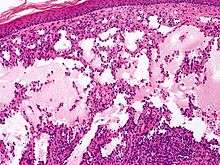

Microscopically, the vesicles in lymphangioma circumscriptum are greatly dilated lymph channels that cause the papillary dermis to expand. They may be associated with acanthosis and hyperkeratosis. There are many channels in the upper dermis which often extend to the subcutis (the deeper layer of the dermis, containing mostly fat and connective tissue). The deeper vessels have large calibers with thick walls which contain smooth muscle. The lumen is filled with lymphatic fluid, but often contains red blood cells, lymphocytes, macrophages, and neutrophils. The channels are lined with flat endothelial cells. The interstitium has many lymphoid cells and shows evidence of fibroplasia (the formation of fibrous tissue). Nodules (A small mass of tissue or aggregation of cells) in cavernous lymphangioma are large, irregular channels in the reticular dermis and subcutaneous tissue that are lined by a single layer of endothelial cells. Also an incomplete layer of smooth muscle also lines the walls of these channels. The stroma consists of loose connective tissue with a lot of inflammatory cells. These tumors usually penetrate muscle. Cystic hygroma is indistinguishable from cavernous lymphangiomas on histology.[6]